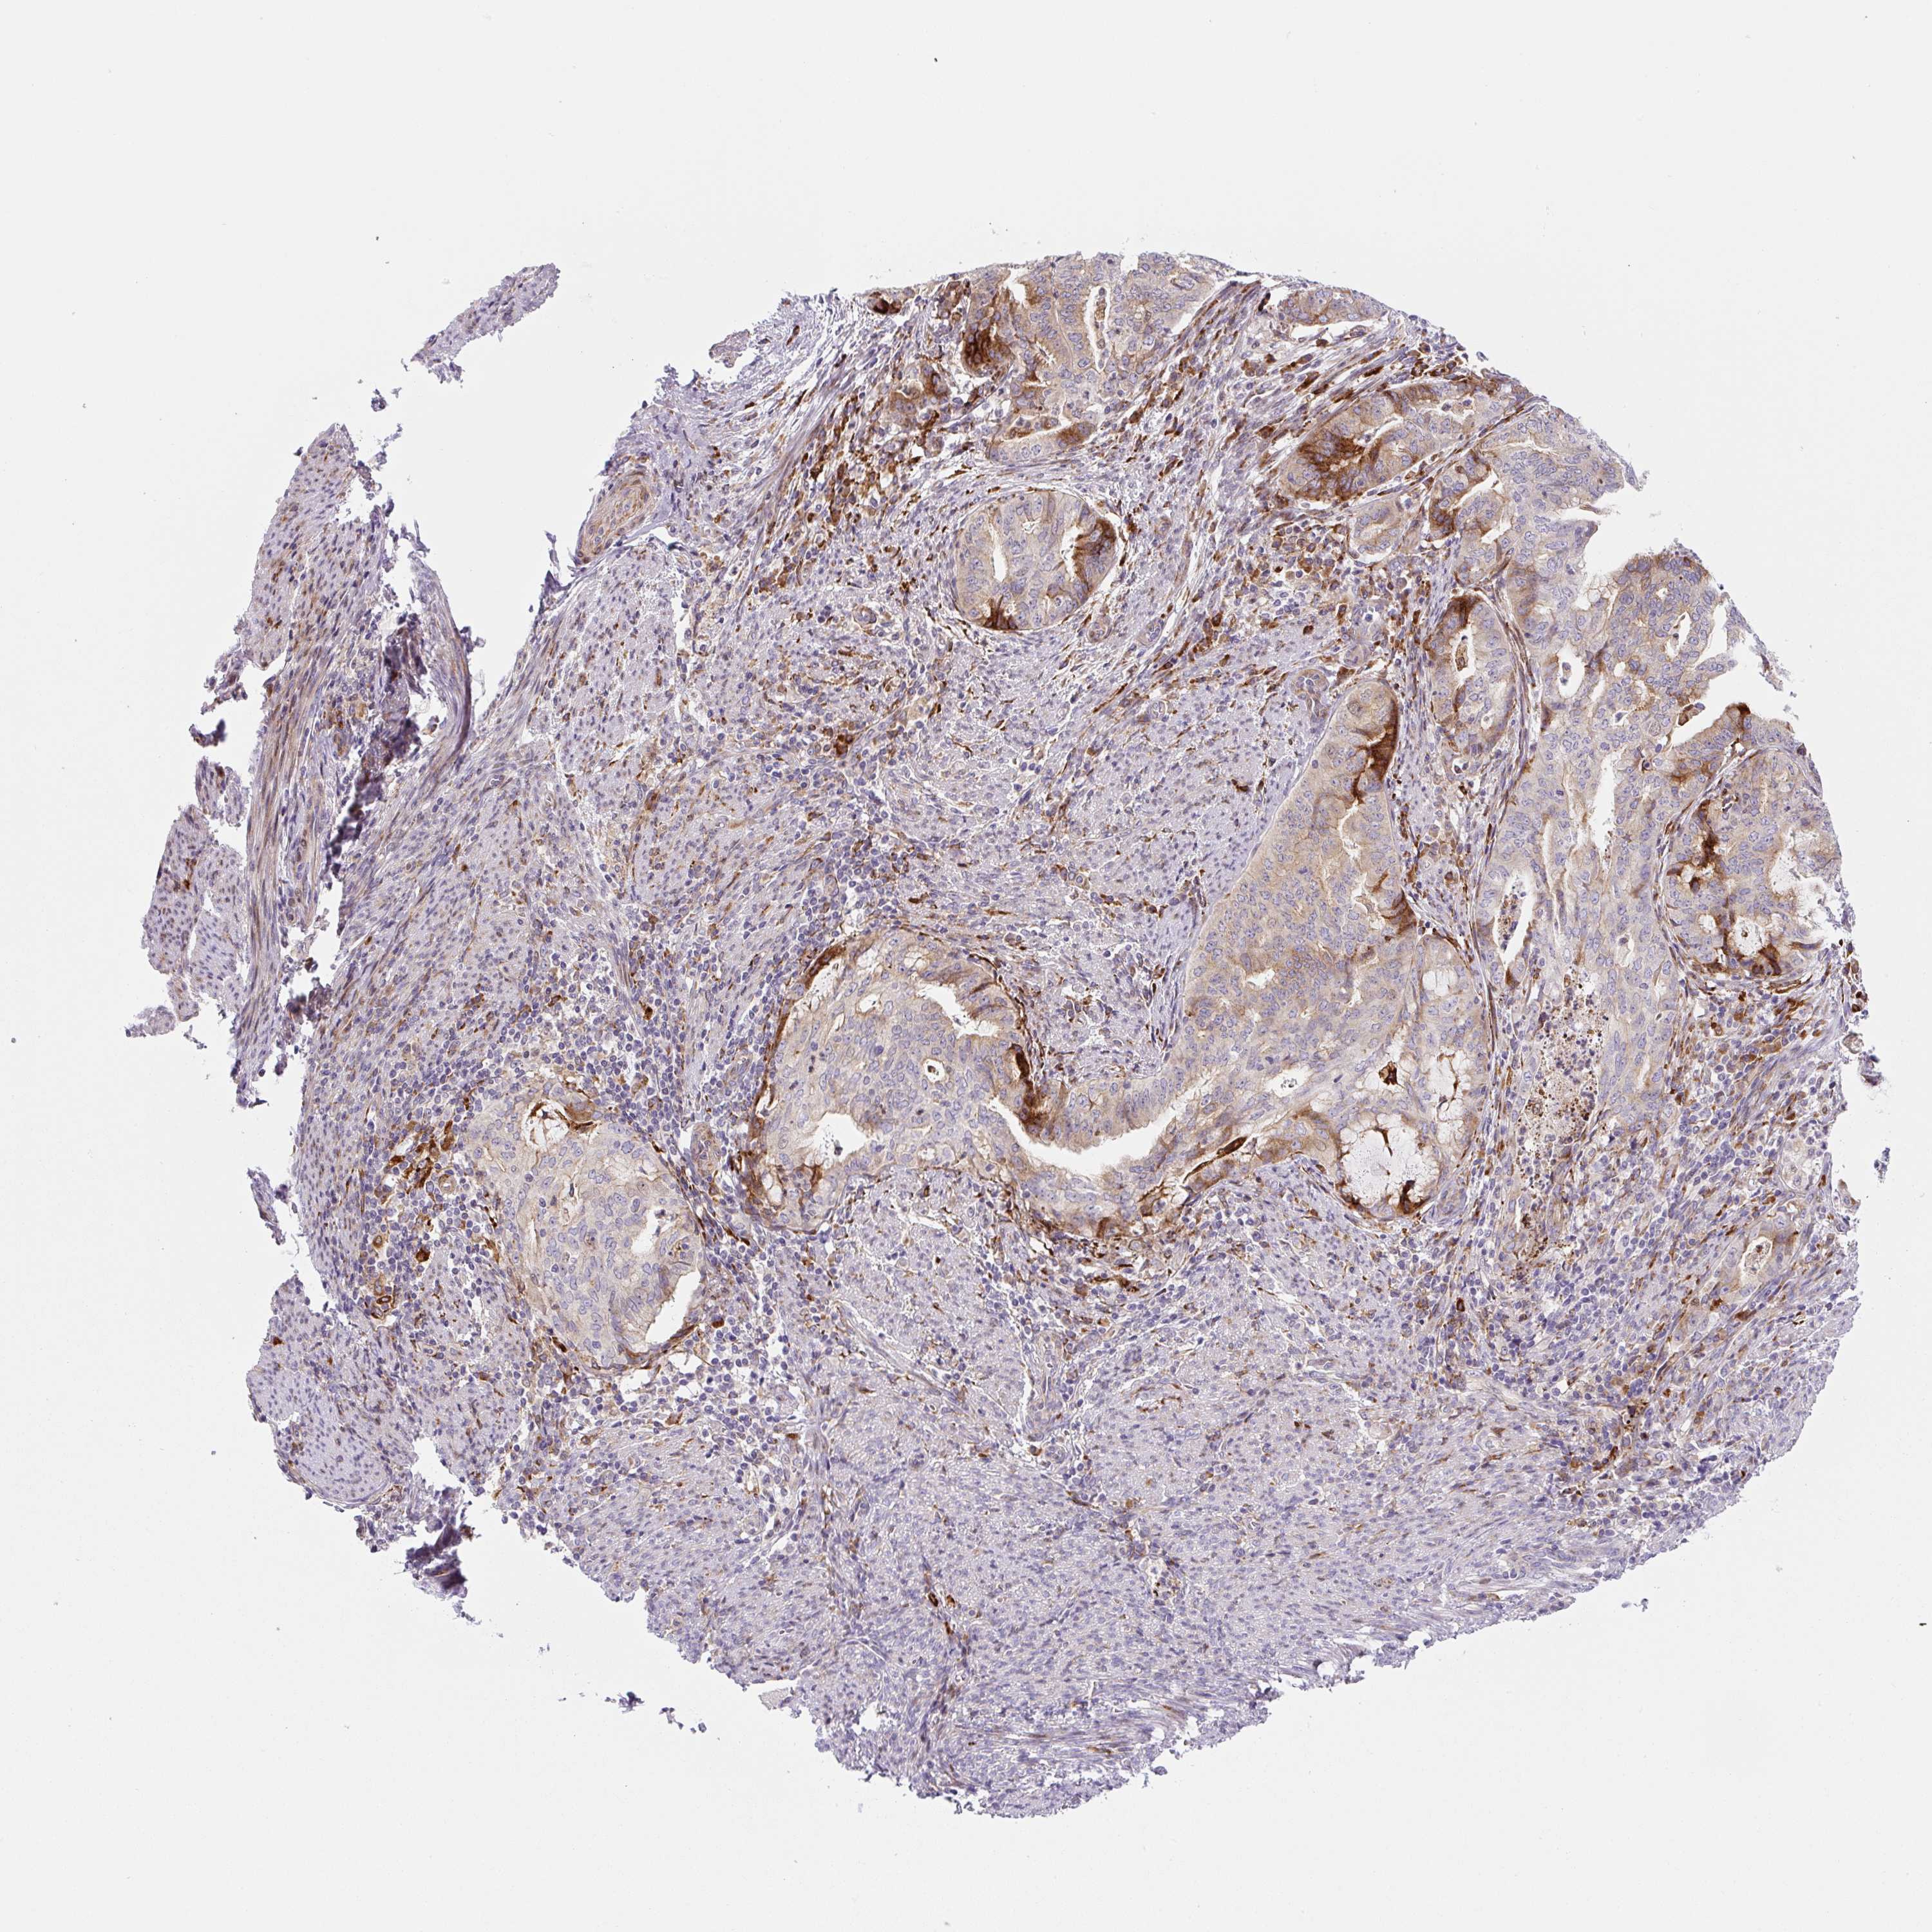

ENDOMETRIAL CANCER - Protein expressioni

A mouse-over function shows sample information and annotation data. Click on an image to view it in a full screen mode. Samples can be filtered based on level of antibody staining by selecting one or several of the following categories: high, medium, low and not detected. The assay and annotation is described here.

Note that samples used for immunohistochemistry by the Human Protein Atlas do not correspond to samples in the TCGA dataset.

Antibody stainingi

Antibody staining in the annotated cell types in the current human tissue is reported as not detected, low, medium, or high, based on conventional immunohistochemistry profiling in selected tissues. This score is based on the combination of the staining intensity and fraction of stained cells.

Each image is clickable and will lead to virtual microscopy that enables deeper exploration of all samples and also displays staining intensity scores, fraction scores and subcellular localization as well as patient and tissue information for each sample.

Antibody HPA054579

Staining

High

Medium

Low

Not detected

Intensity

Strong

Moderate

Weak

Negative

Quantity

>75%

75%-25%

<25%

None

Location

Nuclear

Cytoplasmic/membranous

Cytoplasmic/membranous,nuclear

Adenocarcinoma, NOS

Adenocarcinoma, metastatic, NOS